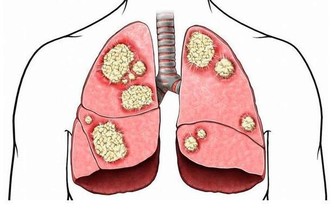

衛生福利部「中華中藥典」2004年的編修資料提到,蓮花是常用的中藥,其荷葉,可降血壓和抗心律失常;其根莖,有解熱、消炎和抗腹瀉的效用。侯玟伊營養師表示,另在韓國的研究中,也發現蓮花具有高含量的生物活性化合物及酚類物質。若適量取蓮藕、蓮子與主食類代換食用,推論有助穩定血糖、減少壞細胞的增殖,維持身體機能正常運作,進而預防癌症。